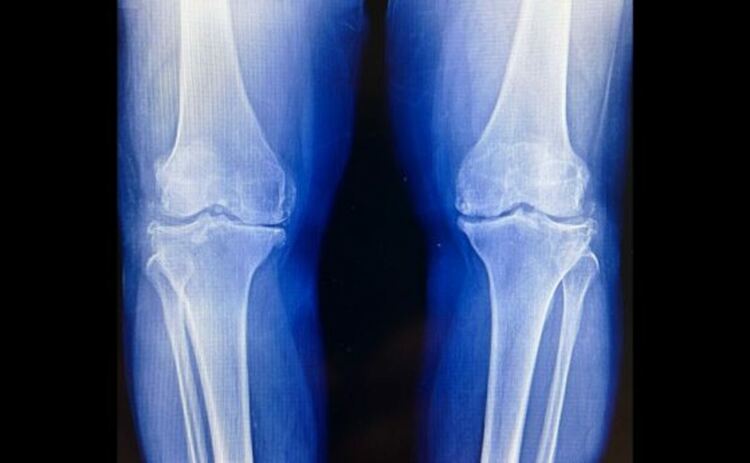

Анализът на походката и измерванията на болката показват, че финото регулиране на ъгъла на стъпалото по време на ходене може да намали болката в коляното, причинена от остеоартрит. Този подход може също да забави прогресията на състоянието - нелечимо заболяване, при което хрущялната възглавница вътре в ставата се разрушава.

Ново проучване на екип от NYU Langone Health, Университета на Юта и Станфордския университет изследва дали промяната в начина, по който пациентите позиционират краката си при ходене, може да намали допълнителното натоварване - стрес върху ставата по време на движение - и да помогне за лечението на заболяването.

Резултатите показват, че тези, които са тренирани да накланят краката си леко навътре или навън от естественото им положение, имат по-бавна дегенерация на хрущяла във вътрешната част на коляното си в сравнение с тези, които са били насърчавани да ходят по-често, без да променят позицията на краката си.